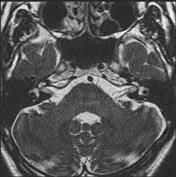

如上图所示,采用3D TSE序列,当TR设置为1500ms的时候,可以发现水并不是太亮。